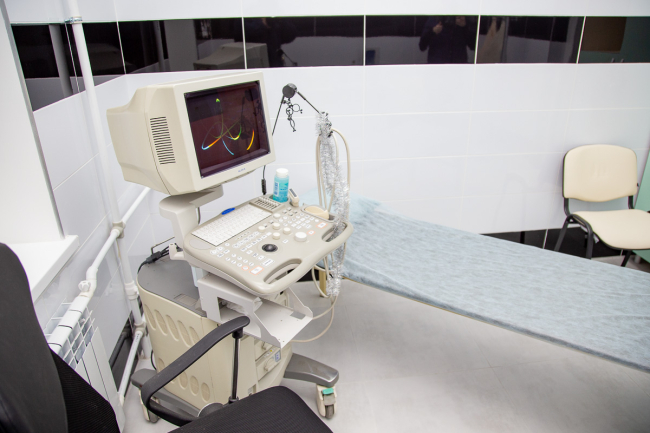

То же самое – и с УЗИ-обследованиями. Пациенту достаточно пройти в соседний кабинет, а не идти в другой корпус больницы.